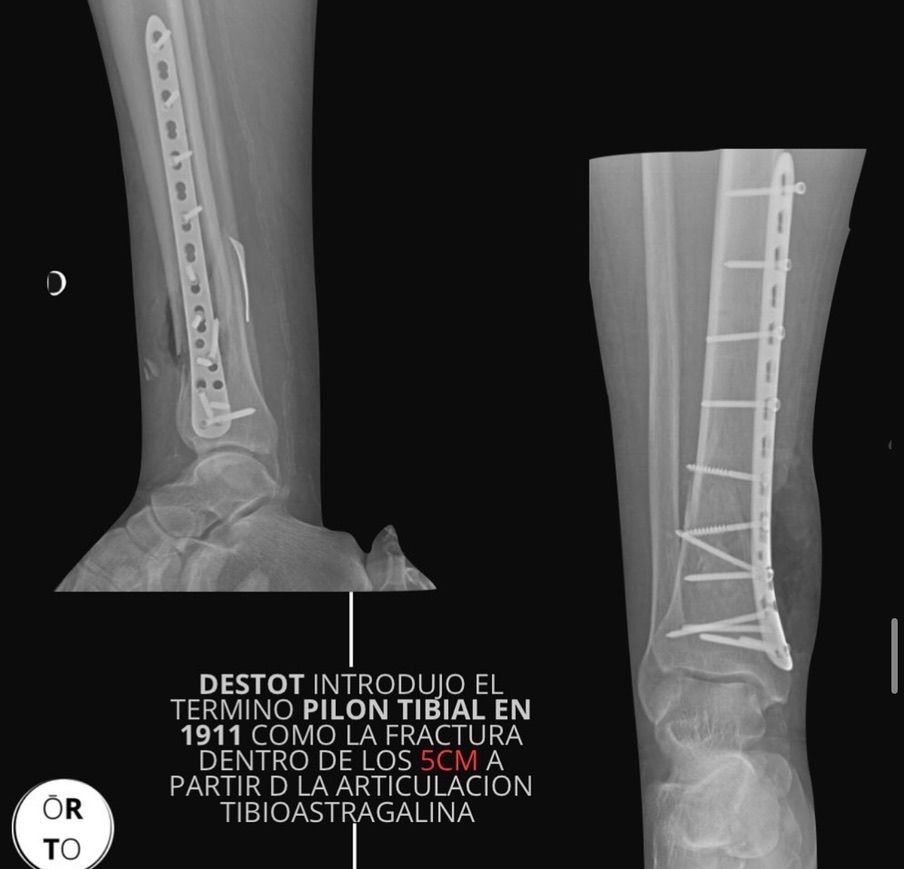

* Fracturas